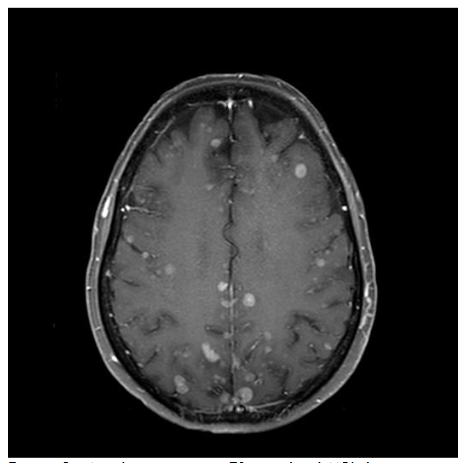

Magnetic Resonance Imaging (MRI)

MRI scanners produce cross-sectional images in various planes and different sequences by adjusting the magnetic field and radio waves and provide superior soft tissue delineation. Through the use of several different sequences, MRI is particularly advantageous for characterizing the internal features and margins of lesions, which enhances the accuracy of distinguishing between benign and malignant conditions and informs more precise diagnosis and treatment planning. In particular, non-fatty malignant lesions tend to be ill-defined, display heterogeneous signal characteristics and low diffusivity, and are often larger. With regards to metastatic lymphadenopathy in the neck, CT is generally more sensitive, while MRI is more specific. Likewise, MRI has high diagnostic accuracy in depicting perineural spread from cancers such as squamous cell carcinoma and can be recognized by enlargement and abnormal enhancement of the affected nerve and effacement of any surrounding fat. MRI is also useful for evaluating intracranial metastases from skin cancers and the extent of disease in neurocutaneous syndromes. The use of intravenous contrast and fat suppression can be helpful for highlighting tumors. Furthermore, diffusion weighted imaging typically demonstrates restricted diffusion in pyogenic abscesses. Microscopy coils can provide higher resolution imaging to better delineate the margins of skin tumors and better define involvement of delicate underlying structures for surgical planning. This technique consists of applying small diameter surface coils over the region of interest. Using μMRI methods, it is possible to produce 3D images with an isotropic resolution of 50 μm and smaller.